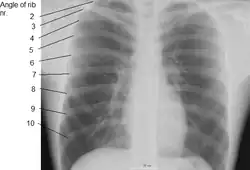

![]() Cutia toracică umană(Source: Gray's Anatomy of the Human Body, 20th ed. 1918) | |

Coastele umane sunt oase plate care fac parte din cutia toracică pentru a ajuta la protejarea organelor interne. Oamenii au de obicei 24 de coaste, în 12 perechi.[1] 1 din 500 de persoane au o coastă suplimentară cunoscută sub numele de coasta cervicală. Toate sunt atașate la partea din spate la vertebrele toracice și sunt numerotate de la 1 la 12 în funcție de vertebrele la care se atașează. Prima coastă este atașată vertebrei toracice 1 (T1). În partea din față a corpului, majoritatea coastelor sunt unite de cartilajul costal la stern. Coastele se conectează la vertebrele de la articulațiile costovertebrale.[2]

Primele șapte seturi de coaste, cunoscute sub numele de "coaste adevărate", sunt atașate la stern de cartilajele costale. Prima coastă este unică și mai ușor de distins decât alte coaste. Este un os scurt, plat, în formă de C, și se atașează la manubriu.[4] Atașamentul vertebral poate fi găsit chiar sub gât la prima vertebră toracică, iar cea mai mare parte a acestui os poate fi găsită deasupra nivelului claviculei. Coastele de la 2 la 7 au un aspect mai tradițional și devin mai lungi și mai puțin curbate pe măsură ce progresează în jos.[5] Următoarele cinci seturi sunt cunoscute sub numele de „coaste false”, trei dintre acestea având o legătură cartilaginoasă comună cu sternul, în timp ce ultimele două (coastele unsprezece și douăsprezece) sunt denumite coaste plutitoares.[1] Ele sunt atașate numai la vertebre și nu la stern sau cartilaj care iese din stern.

În general, coastele umane cresc în lungime de la coasta 1 până la 7 și scad din nou în lungime până la coasta 12. Împreună cu această schimbare de dimensiune, coastele devin progresiv oblice (înclinate) de la coasta 1 la 9, apoi mai puțin înclinat până la coasta 12.[5]